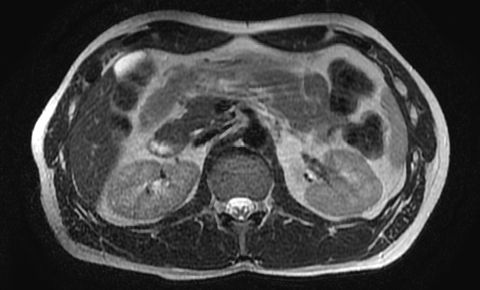

白色文字(排除指定关键词) Imaging Anatomy: interactive PACS-like atlas of radiological anatomy

解剖学模块